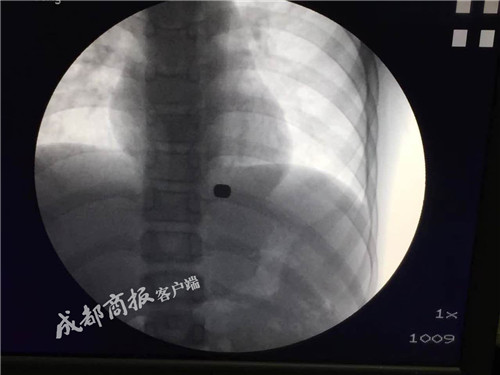

剧烈的胸、腹痛持续10天后,13岁的贵州少年强强终于在四川大学华西医院取出了卡在胃里的两块磁铁,避免了开胸的大手术。而让他陷入险境的,是一支“磁性笔”。

伴随着胸腹部传来的剧痛,小强将自己误吞磁铁的事情告诉了父母。到医院一检查,才发现跌落在小强食管下段贲门处的磁铁,与掉落在胃底的磁铁隔着胃底肌层紧紧相吸,同时还凿出一个0.1厘米的穿孔。因为长时间停留,贲门和胃底部的组织已经将两块磁铁“包裹”起来,磁铁深深嵌入肉里,根本看不到磁铁的边缘。此时医生的建议是:开胸手术,取出磁铁。而父母担心强强年龄过小,无法承受如此大的手术,于是辗转云贵两省多家医院,无奈都得到了相同的答案:只能开胸。

11月7日上午11点,麻醉后的强强被推进手术室,胡兵先用内镜从他的食道伸进去,轻轻拨开包裹着两块磁铁的组织,然后再把严格消毒后的“磁王”套上一根细线,用内镜缓缓送到强强体内的磁铁旁。不出所料,一个小时后两块磁铁被成功取出。